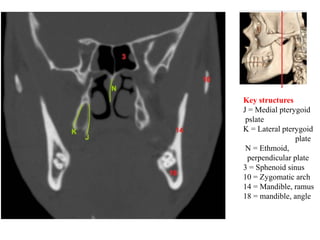

Key structures

J = Medial pterygoid

pslate

K = Lateral pterygoid

plate

N = Ethmoid,

perpendicular plate

3 = Sphenoid sinus

10 = Zygomatic arch

14 = Mandible, ramus

18 = mandible, angle